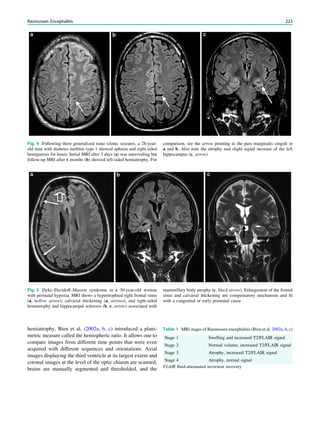

using magnetic resonance (MR) scanners with a magnetic

field strength B0 of at least 1.5 Tesla. Theoretically and in

clinical practice however, 3 Tesla scanners have advantages.

2 Theoretical Considerations

In accordance with the increasing number of parallel spins at

higher field strengths, the MR signal is proportional to

the magnetic field strength B0 (signal-to-noise ratio propor-

tional to B0). The signal theoretically doubles from 1.5 to 3

Tesla; in reality, it increases by a factor of around 1.7–1.8.

This signal gain can be utilized to increase the contrast-to-